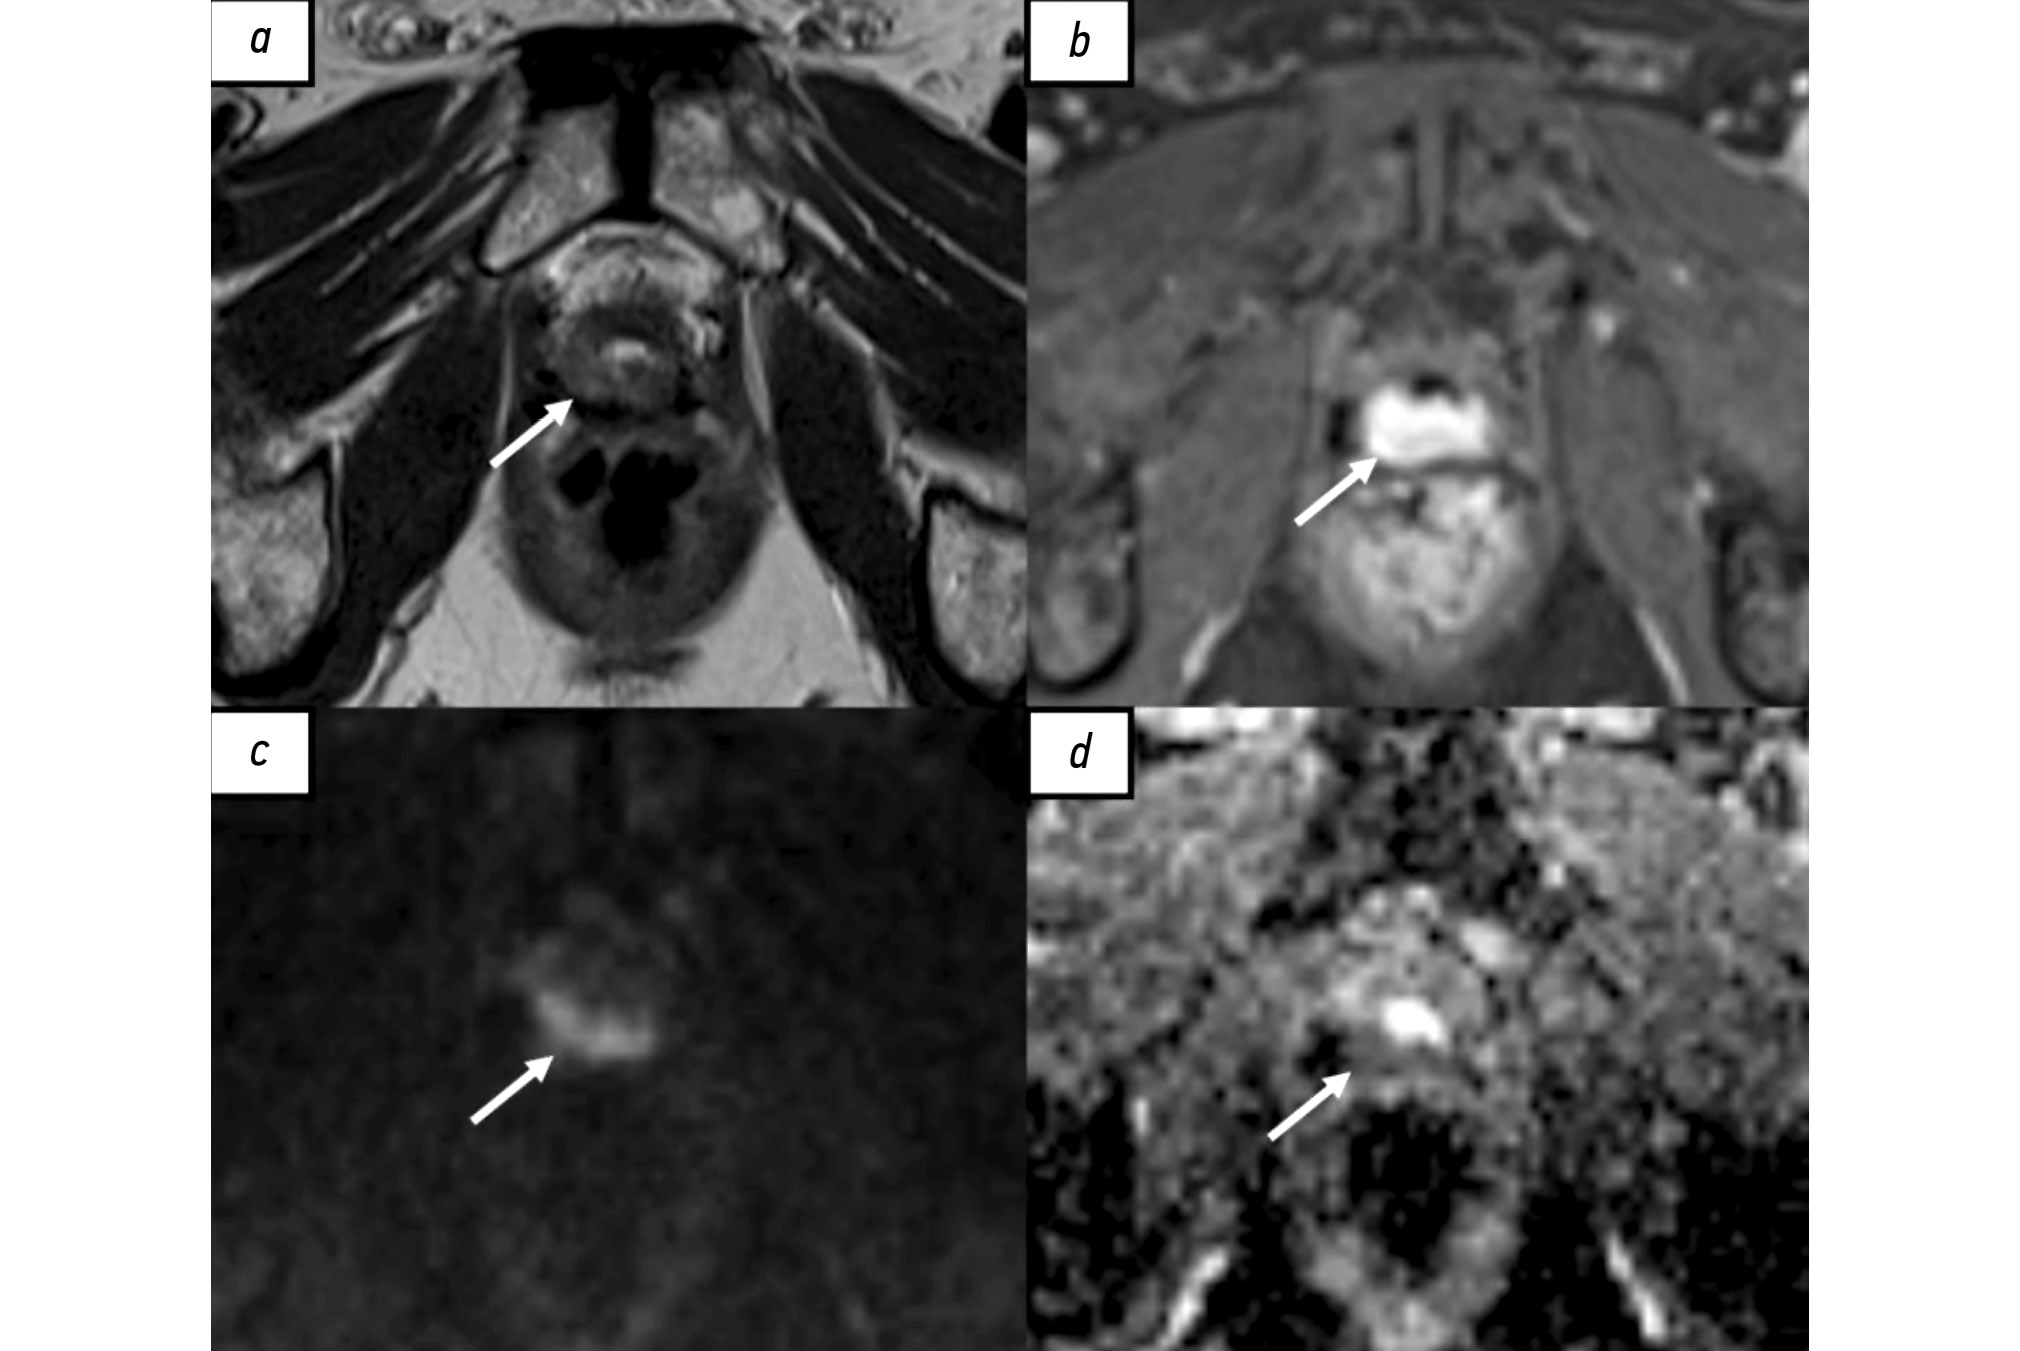

自身免疫性垂体炎:COVID-19 大流行期间的病例观察

垂体炎是一种罕见的炎症性疾病,其特征是垂体及其柄的受累。该病可能由垂体组织浸润、自身免疫因素、感染性疾病或其他未明原因引起。由于某些垂体肿瘤(如垂体腺瘤和转移瘤)可能具有相似的临床特征,因此该病的临床诊断具有挑战性。磁共振成像是诊断疑似垂体炎以及鉴别腺垂体炎(前叶受累)与漏斗-神经垂体炎(垂体柄和后叶受累)的主要方法。垂体炎可分为原发性(自身免疫性)和继发性。继发性垂体炎可能继发于局灶性病变 (如肉芽肿、囊肿或腺瘤)或系统性疾病(如结节病、肉芽肿性多血管炎)。其临床表现受多种因素影响,其中之一是基础治疗。临床病例已有相关文献报道。

本文报道了一例 37 岁女性患者的临床病例,该患者既往诊断为高泌乳素血症,并接受卡麦角林对症治疗。患者被转诊进行磁共振成像检查,结果显示垂体信号不均匀。2021年7月随访磁共振成像显示垂体信号不均且增大。2021年12月,患者感染COVID-19并发生重度肺炎,接受糖皮质激素治疗及氧疗。2022年5月磁共振成像检查显示垂体明显增大且信号不均。在使用泼尼松(晨 10 mg,晚 5 mg)治疗后,患者的临床及影像学表现显著改善。

患者随访至COVID-19 大流行结束。对于此类患者,影像学结果的解读和治疗方案的选择可能受到新冠病毒感染及其治疗的影响。

在评估垂体炎的病程及其影像学变化时,医生应考虑 COVID-19 相关治疗,尤其是糖皮质激素对疾病的影响。